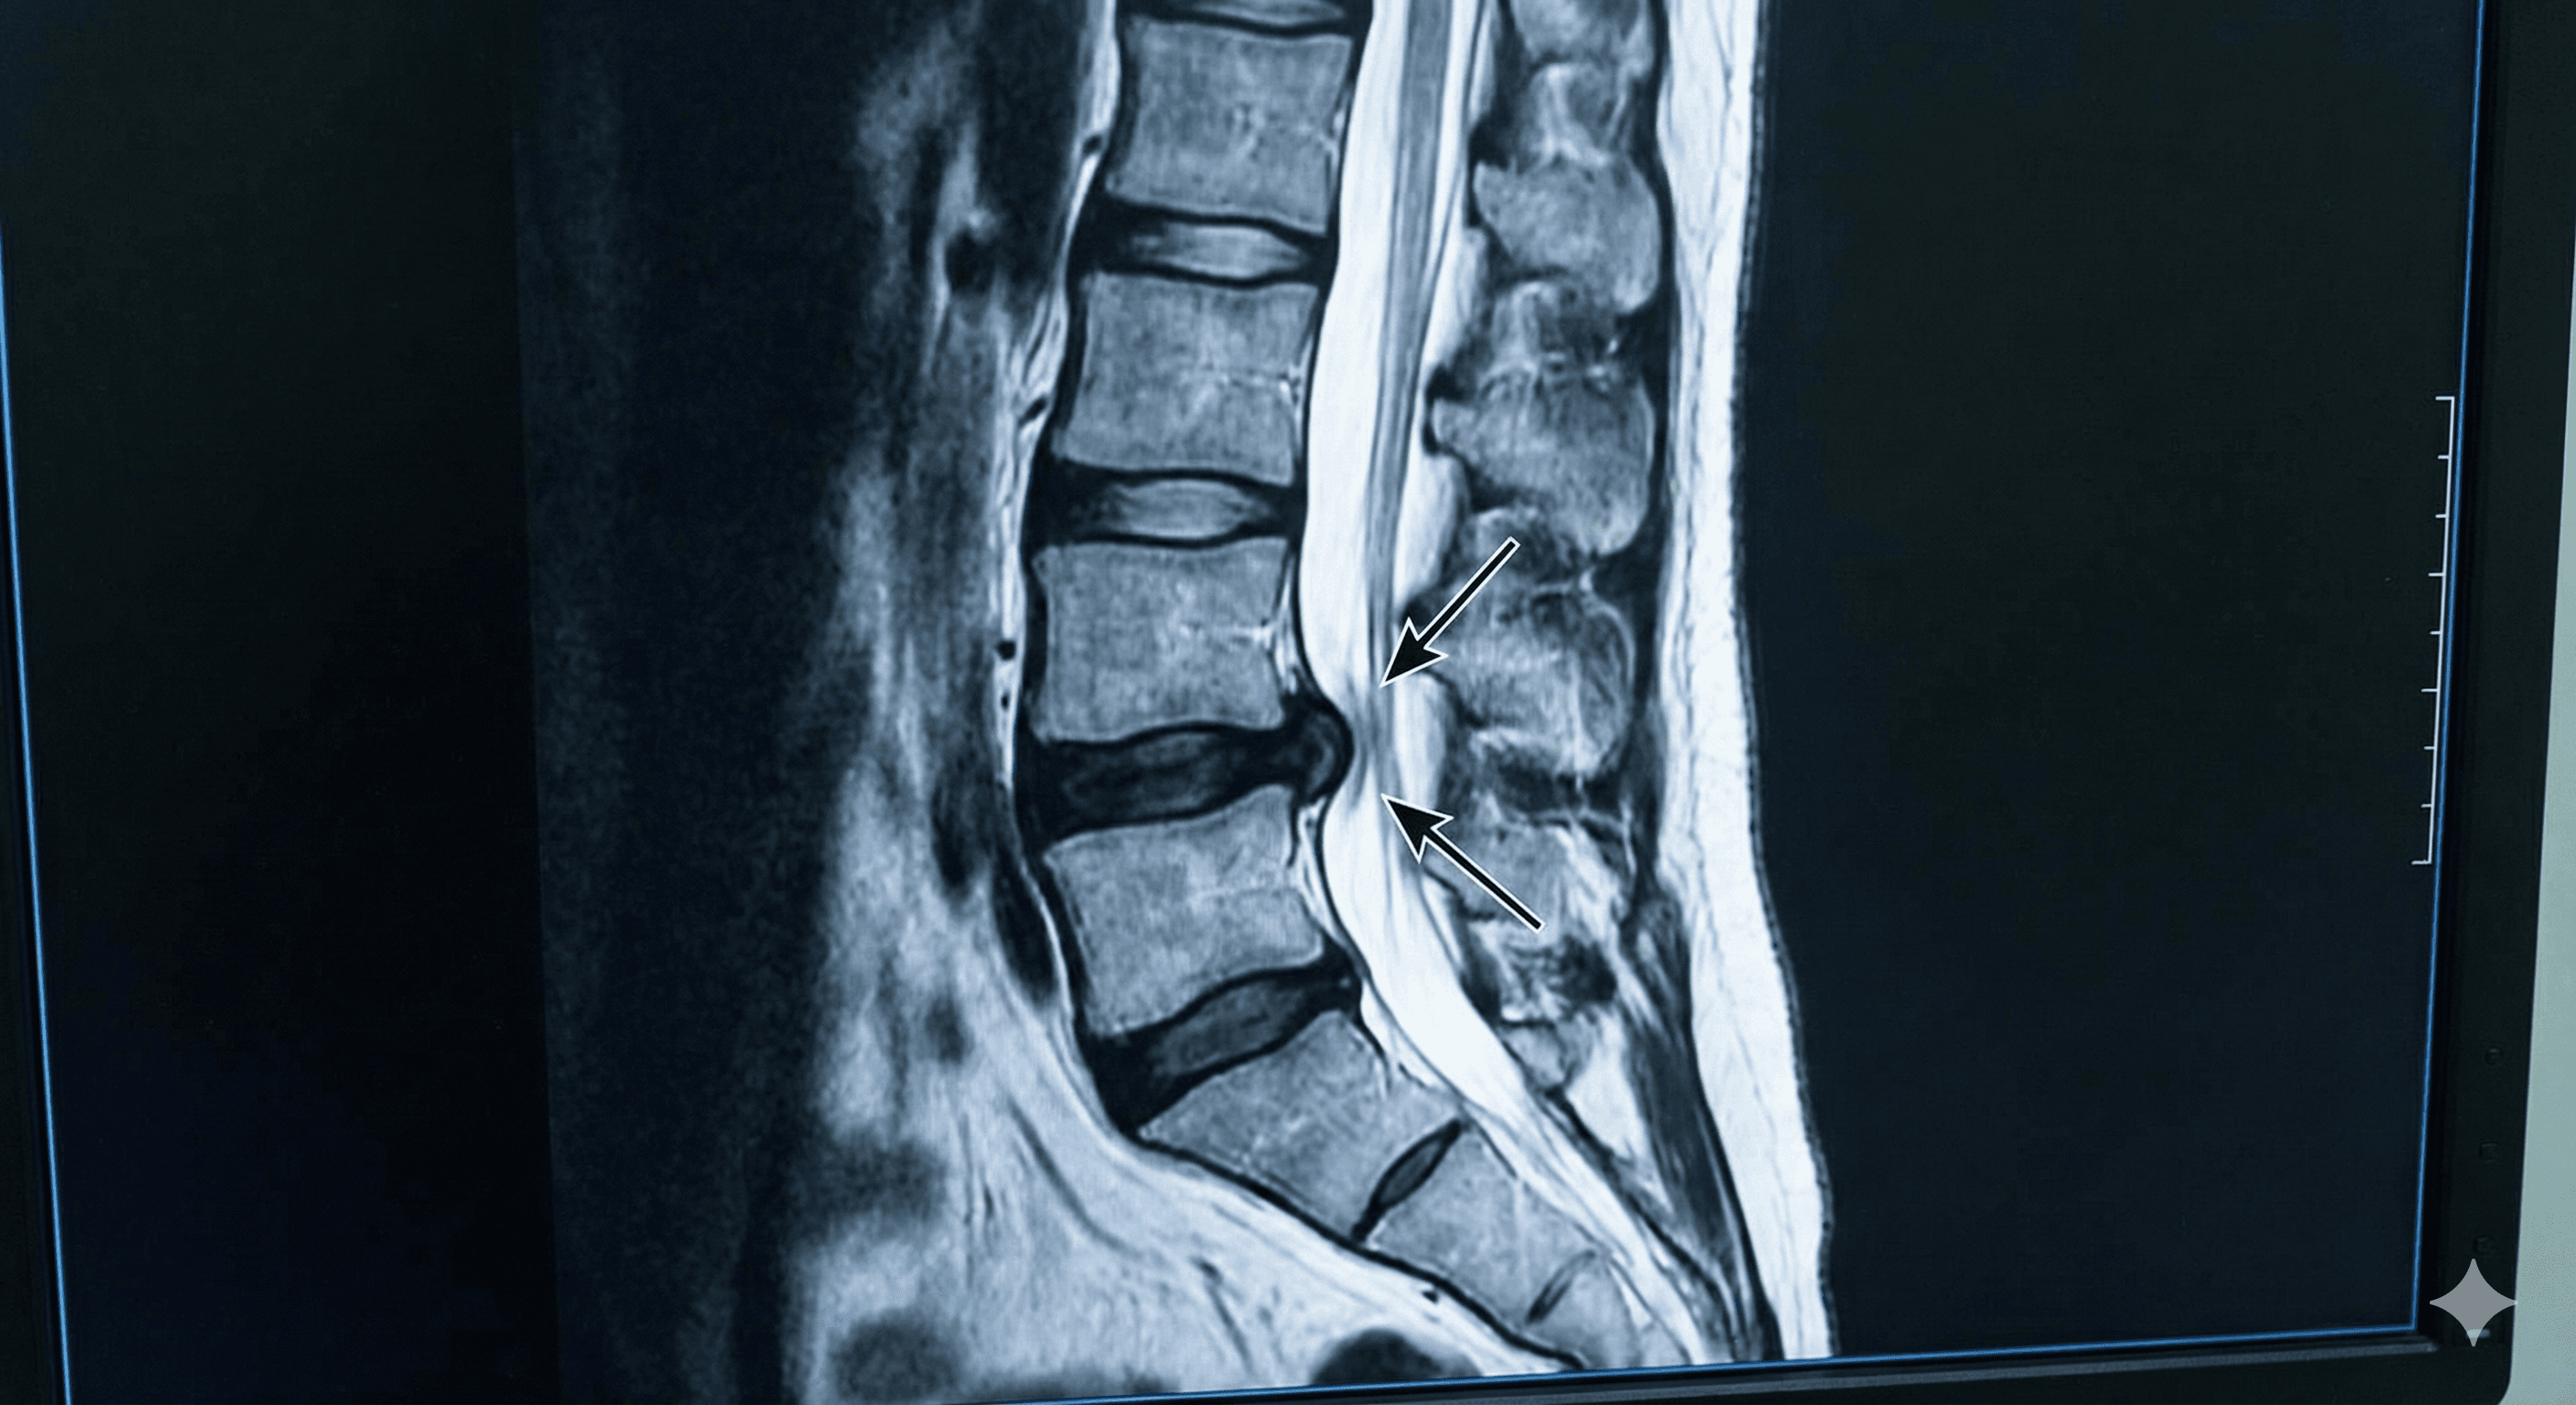

Desplazamiento del núcleo de un disco intervertebral que comprime los nervios de la columna, causando dolor de espalda.